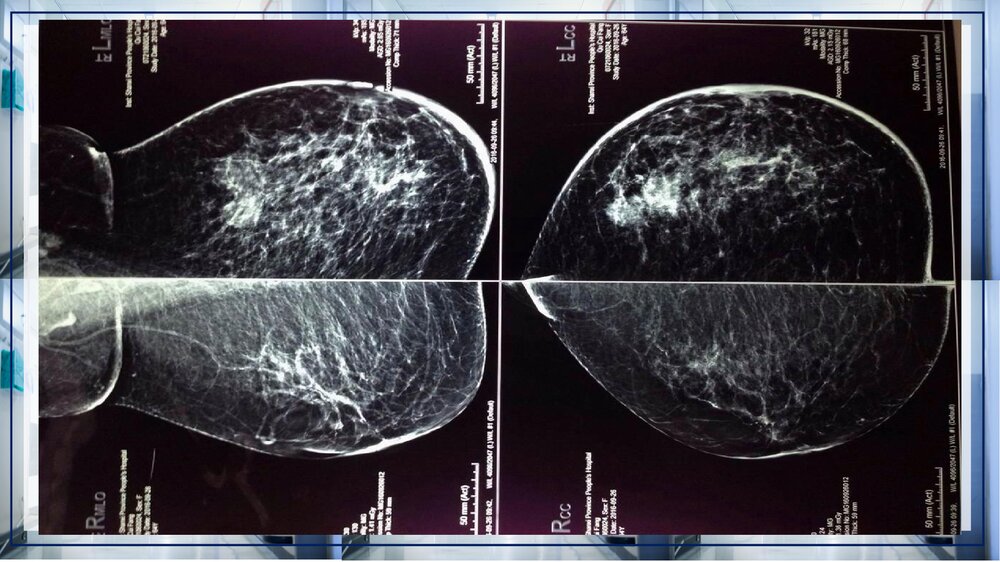

关于乳腺癌病例讨论关于乳腺癌病例讨论XXX:凡心20XX年X月XX日病史女性,52岁,发病急。发现左乳皮肤红肿2个月。患者入院前2月余,无意间发现左乳皮肤红肿,偶有乳房疼痛,门诊手诊可触及左乳外上片状增厚区,乳腺钼靶示左乳多发结节,BIRADS4b,右乳未见异常。既往史1998年因子宫肌瘤行子宫全切术;高血压病史17年,平素口服尼群地平、硝酸异山梨酯,自诉血压控制可;糖尿病病史15年,平素口服二甲双胍、格列本脲,自诉血糖控制可。专科检查双乳外形不对称,左乳明显增大,双乳头无内陷及偏移,左乳外上方可触及片状增厚区,范围约3.5*3㎝²,质硬,边界不清,活动度尚可,无压痛。左乳下方可见橘皮征,范围约20*22㎝,局部皮肤略红,皮温增高,右乳正常。左腋下可触及一肿大淋巴结,大小约1*1.5㎝²...